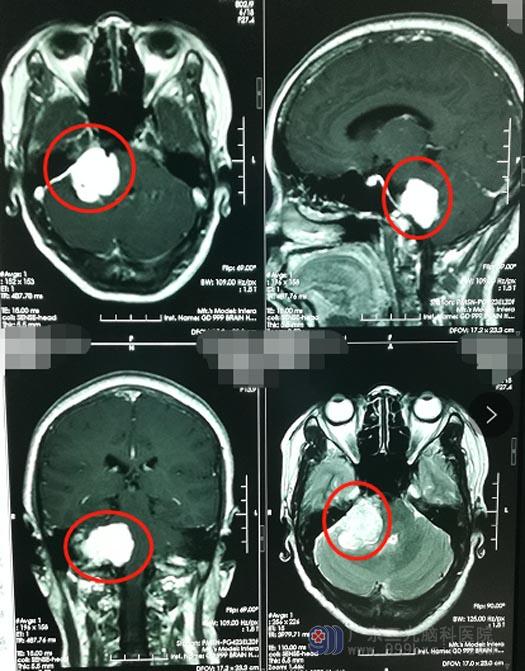

年过半百的李阿姨,5年前就开始右耳不好使,她自己和家人都理所当然地认为:人老了,耳背很常见。直到一个月前,李阿姨开始头痛,痛得浑身出冷汗,才和家人来到广东三级脑科医院检查;脑部影像检查发现颅内有一3cm×4cm×4cm大小的肿瘤,诊断为:右侧桥小脑角占位,考虑脑膜瘤, 入住神经外五科。

李阿姨的脑肿瘤已经累及右侧内听道,并包绕着具有重要供血作用的右侧椎动脉,同时脑干、右侧小脑半球已经受到压迫,第四脑室受压变窄;如果肿瘤继续生长,还会进一步压迫、粘黏甚至损伤三叉神经、面神经、脑干、小脑、后组颅神经等,患者可能会出现继发性三叉神经痛、面瘫、小脑共济失调、走路不稳、吞咽困难、饮食呛咳等症状,造成脑脊液循环障碍,可以产生脑积水,严重的头痛、呕吐、视乳头水肿等,甚至可以出现意识障碍,危及生命。